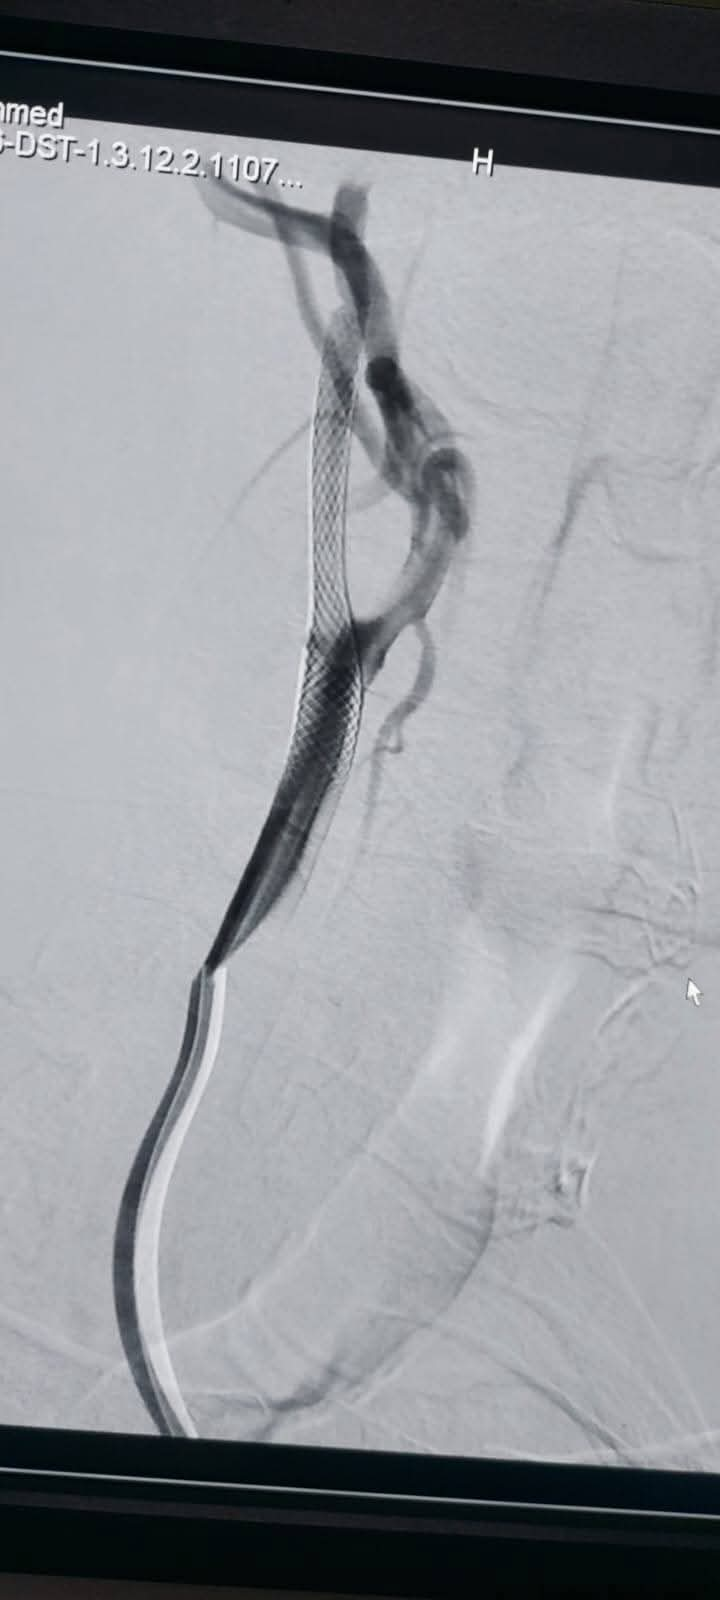

واستقبل المستشفى الرئيسي مريض يبلغ من العمر 65 عامًا، يعاني من جلطات متعددة بالمخ؛ نتيجة ضيق حرج بالشريان السباتي، وبعد إجراء الفحوصات اللازمة تقرر ضرورة التدخل بالقسطرة.

تشكل الفريق الطبي الذي جاء برئاسة الأستاذ الدكتور مصطفى هاشم أستاذ الأشعة التشخيصية والتداخلية والقسطرة المخية، يعاونه الدكتور محمود رفعت مدرس واستشاري الأشعة التشخيصية والقسطرة المخية، والدكتور محمود نجيب مدرس واستشاري الأعصاب والقسطرة المخية، والطبيب عبد الرحمن عمر مدرس مساعد الأشعة التشخيصية والتداخلية.

وتكللت العملية بالنجاح، وغادر المريض المستشفى بحالة صحية مستقرة .